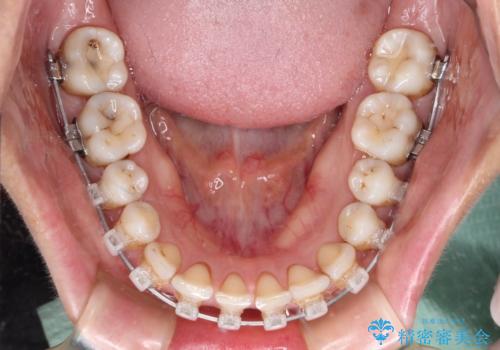

- 隙間の空いた前歯をセラミッククラウンで補隙したところ、歯肉から出血してしまい、何とかしたいとのことで来院された患者様です。

初めは前歯のみの処置で改善を希望されていたため、広範囲に処置範囲を広げることで歯の幅がバランスする治療を提案しましたが、削らなければならない歯が増えてしまうため、患者様と相談して全顎矯正により前歯のスペースを閉じていくこととしました。

不適合なクラウンが装着されていたため、歯周ポケットが深くなっていましたので、矯正治療前に歯周外科処置を行って歯周ポケットを除去し、矯正治療後にオールセラミッククラウンにて補綴治療を行うこととしました。